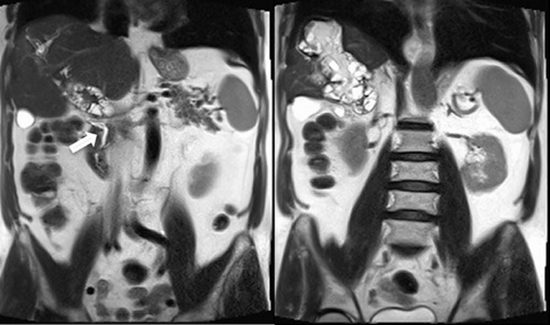

Liver hydatidosis disease with portal vein invasion: Report of a rare case and review of literature

Hydatid disease is a zoonosis caused by Echinococcus granulosus. Humans are aberrant intermediate hosts and following the infection, the parasite may infest any organ of the body, with the liver and lungs being the most involved organs. Portal vein involvement by hydatid cyst disease is extremely rare with only seven cases published to our knowledge. We present a 62-year-old Persian male with an incidental liver cyst. His laboratory tests were in normal ranges. The ultrasonography (US), computed tomography (CT) and magnetic resonance imaging (MRI) findings show hydatid disease of the liver with distal portal vein involvement and collateral venous formations. The patient is being followed and has not gone under surgery yet. It possesses a propensity to invade multiple organ systems, notably the liver and lungs. Hydatid disease is imposing a significant burden on healthcare systems specifically in developing countries. Manifestations of the disease are often non-specific, while a subset of the infected population remains asymptomatic. Portal vein invasion and obstruction is a rare complication, and it is important to distinguish it from vein thrombosis, as the management of these entities requires different approaches.